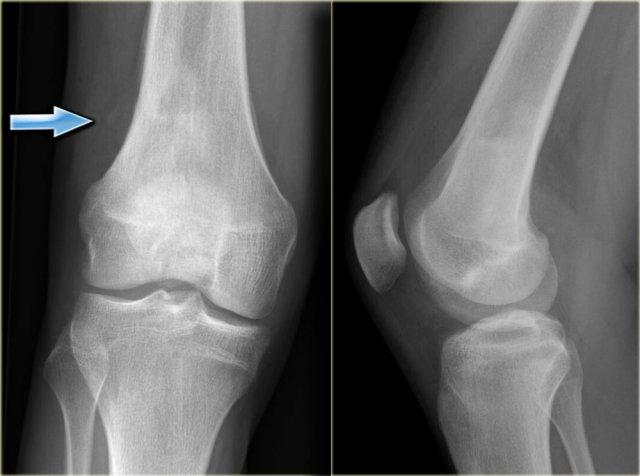

Đây là phát hiện tình cờ về một số tổn thương xơ cứng lệch tâm ở đầu xa xương đùi.

These are inert filled-in non-ossifying fibromas.

No further examination is needed.